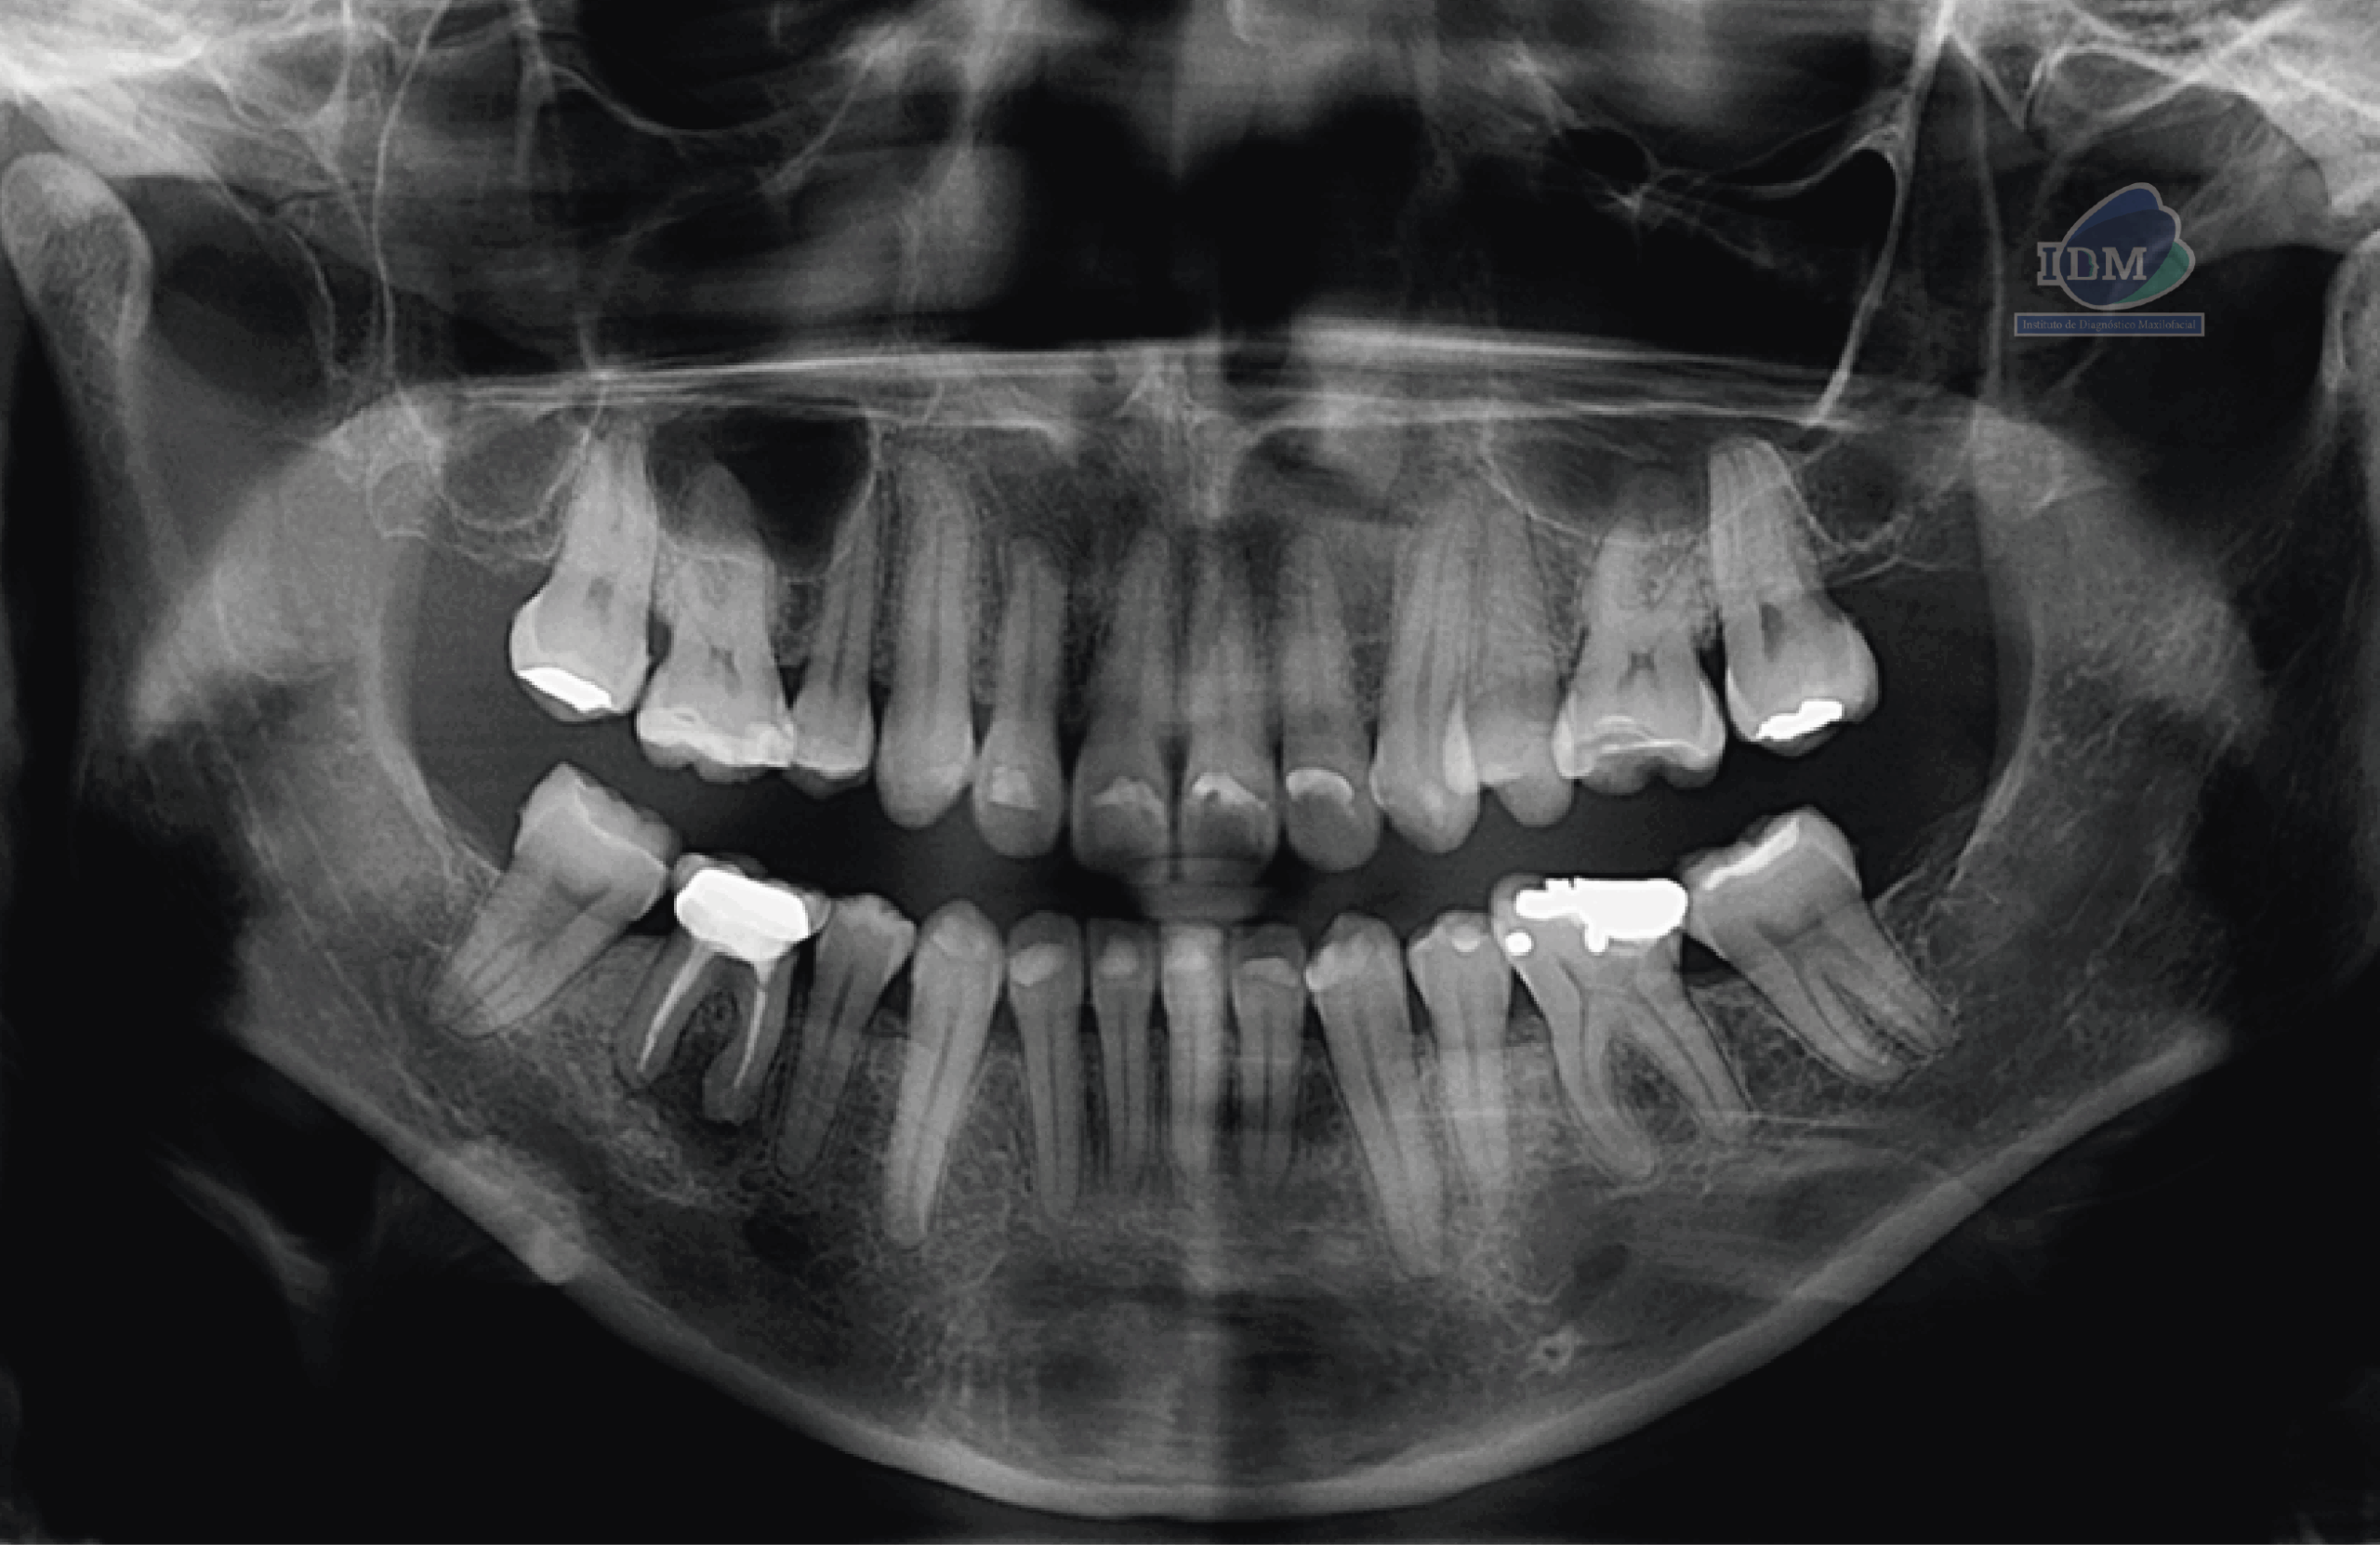

Paciente femenina de 36 años, es referido al Instituto de Diagnóstico Maxilofacial – IDM (Sede Surco) para evaluación de pieza 46 con tratamiento endodóntico.

En la radiografía panorámica se evidencian múltiples restauraciones coronarias, así como presencia de placa cervical mineralizada de forma generalizada.

En relación con la pieza 46, se observa tratamiento endodóntico, hipercementosis y un proceso osteolítico periapical, que presenta un aumento de la densidad ósea circundante.